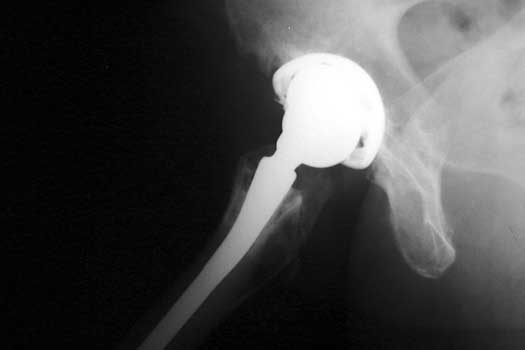

Metal liner dislocation. Model of total hip replacement components positioned with metal  liner dislocated.